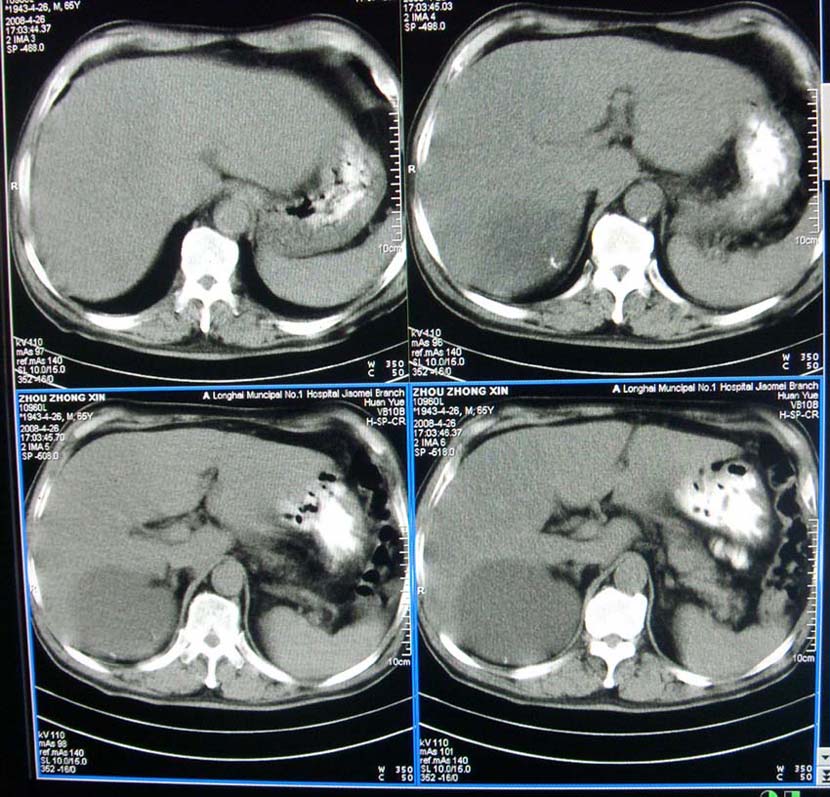

以下是引用liangshusheng在2008-4-27 13:28:00的发言:[br]双肾都有结石,右肾积水波浪状,输尿管积水,建议往下扫

以下是引用zjzjr在2008-4-27 14:25:00的发言:[br]1,右侧多发囊性占位,考虑囊肿可能大。[br]2,肾下部输尿管走行区囊性占位,巨输尿管?建议mru。